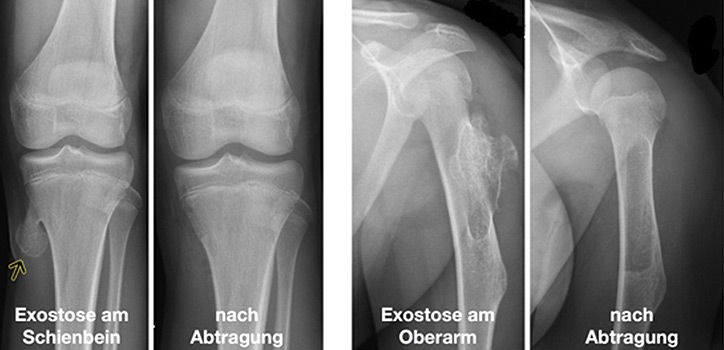

Exostosen

Unter Exostose versteht man eine abgegrenzte Zubildung von kompakter Knochensubstanz mit Wachstum nach außen. Sie können an den verschiedensten Knochen auftreten und ein breitbasiges oder spornhaftes Wachstum aufweisen. Bei der sogenannten Exostosenkrankheit treten viele verschiedene Knochentumoren auf, bei denen eine bösartige Entdifferenzierung nicht vollkommen ausgeschlossen ist. In der Regel finden sich jedoch einzelne Exostosen, insbesondere am Knie, die mit der chirurgischen Entfernung bei o.g. Beschwerden therapiert sind.